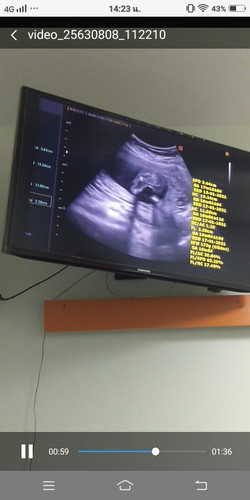

ซาวตอน17w2d. เป็นผู้หญิงรึผู้ชายคะ.

น่าจะลูกสาวค่ะแม่ ไม่เห็นจู๋โผล่

รูปเบลอมากค่ะ แต่คิดว่าน่าจะสาว